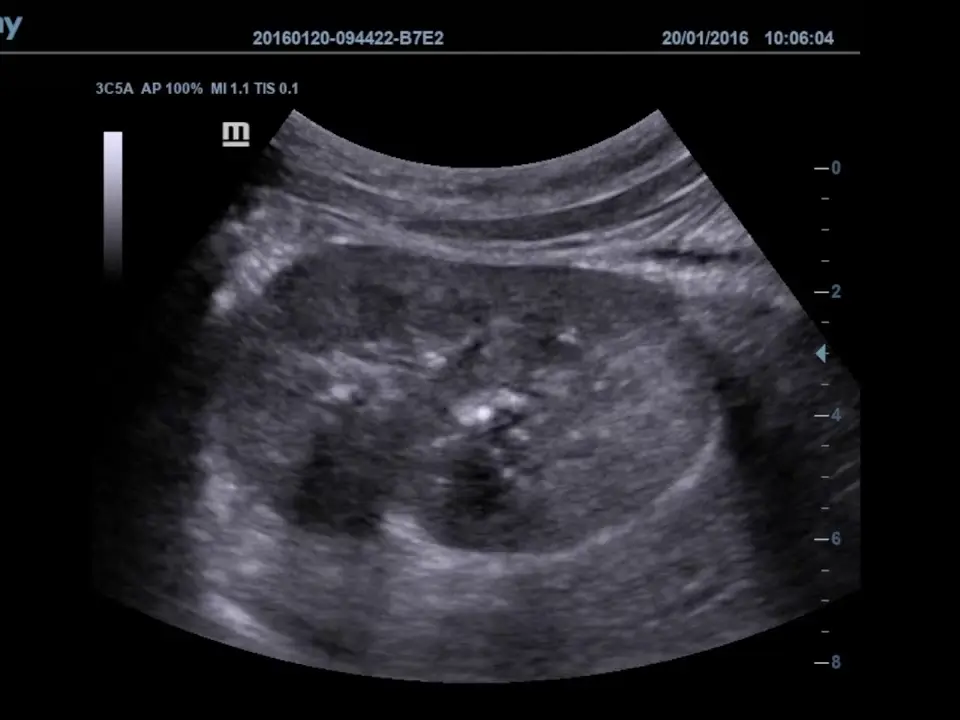

Una paciente en gestación temprana acudió a su primera ecografía obstétrica. El estudio, realizado por vía abdominal, no mostró estructuras gestacionales. Con base en estos hallazgos, se planteó un diagnóstico de posible aborto espontáneo o embarazo anembriónico (tipo de aborto espontáneo en el que se forma el saco gestacional y la placenta, pero nunca se desarrolla un embrión). No obstante, sus niveles hormonales indicaban que la gestación continuaba. La paciente buscó una segunda opinión, lo que cambió por completo la historia clínica.

Días después, se realizó una ecografía transvaginal utilizando un ultrasonido de alta resolución DC-70 de Mindray, en la cual se observa un saco gestacional intrauterino con polo fetal (la primera señal visible en ecografía de que el embarazo está en el útero y el bebé ya empieza a formarse), y una edad gestacional estimada de 5 semanas y 6 días, sin signos de pérdida.